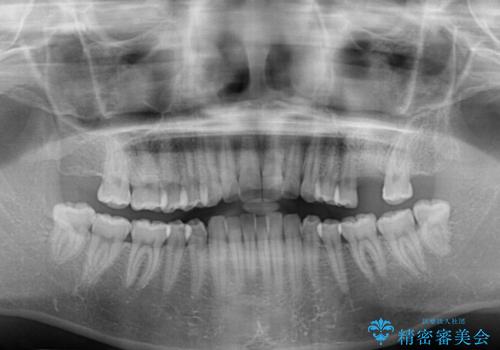

- 抜歯が必要と診断された奥歯を気にして来院された患者様です。

抜歯の上インプラントによる補綴治療を行うこととなりましたが、前歯の叢生も気になるとのことで並行して矯正治療を行うこととしました。

歯列不正は軽微であったので、インビザラインによる矯正治療とし、矯正治療中にインプラント埋入を行う予定としました。